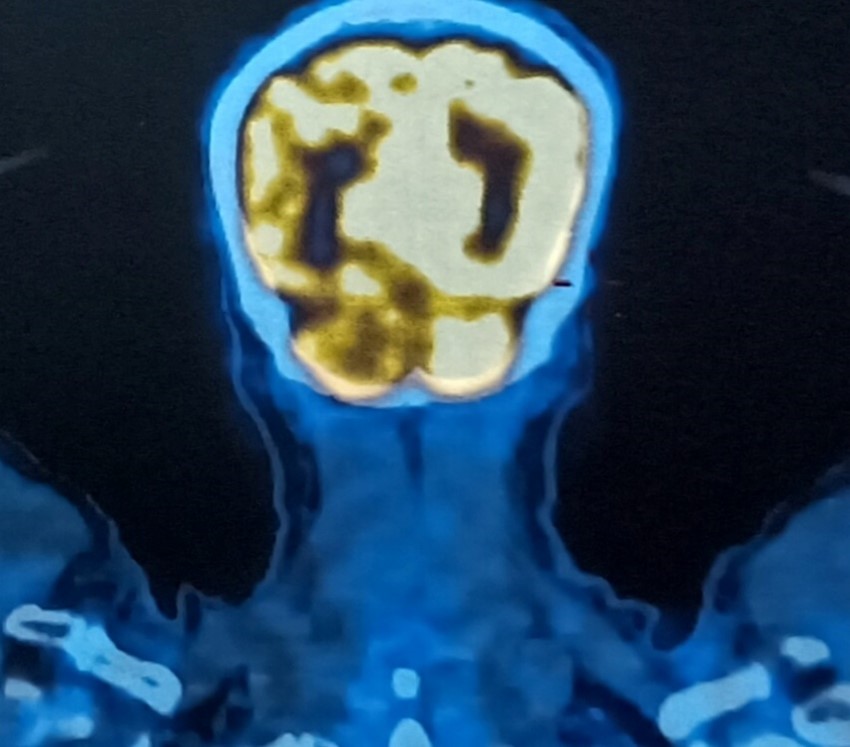

- Bệnh nhân được chụp PET/CT (Positron Emission Tomography and Computed Tomography hay chụp cắt lớp ghi hình positron.

Hình 6: Hình ảnh chụp PET/CT: Hình ảnh khối ở gan hạ phân thùy III kích thước 36x66x71mm, tăng chuyển hóa FDG (SUV max= 7,3) (bình thường nhỏ hơn 2,5) (mũi tên đỏ) (FDG là một dược chất phóng xạ dùng trong chụp cắt lớp ghi hình positron, SUV max là giá trị hấp thu tiểu chuẩn tối đa FDG, tăng cao chuyển hóa FDG hướng tới gợi ý tổn thương ác tính). Không phát hiện hình ảnh tăng chuyển hóa FDG tại vị trí gan phải (tổn thương u gan cũ đã SIRT). Hình ảnh tăng chuyển hóa FDG tại cánh xương cùng, nghĩ đến do di căn (SUV max= 4,5) (mũi tên xanh).

Hình 7: Hình ảnh chụp PET/CT: Không thấy hình ảnh tăng chuyển hóa FDG tại vùng thái dương chẩm trái (vị trí đã phẫu thuật ung thư hắc tố ác tính).